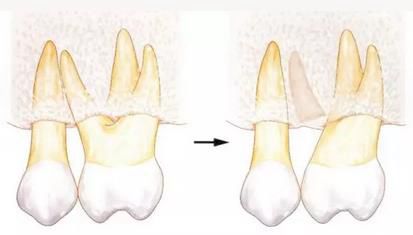

[針對(duì)牙根接近的牙周外科處理--牙體成形]

牙根一般根尖側(cè)較細(xì),所以牙根接近會(huì)使根尖部分減少。進(jìn)行牙周外科處理時(shí),如果能夠?qū)⒐墙M織切除一部分的話,就能通過(guò)骨組織切除和牙體成形來(lái)解決牙根接近的問(wèn)題。

▲圖6

如果可以在一定程度上削除骨組織的話,就可以通過(guò)牙體成形和骨外科處理來(lái)獲得biologic width,并可以解決牙根接近的問(wèn)題。